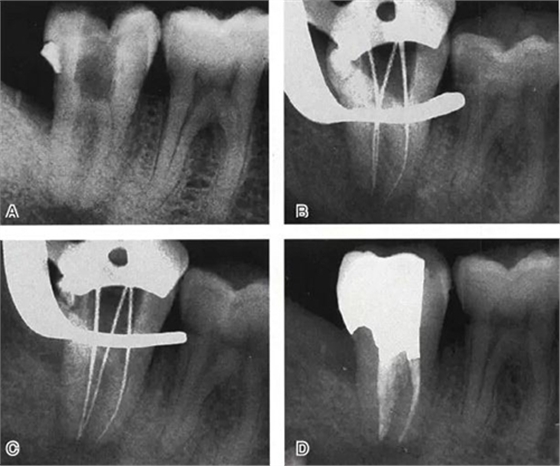

圖4 Ⅰ型C形根管治療典型病例一,A:初始片,B:初尖銼片,C:主尖銼片,D:充填片

圖5 Ⅰ型C形根管治療典型病例二,A:初始片,B:初尖銼片,C:主尖銼片,D:充填片

圖6 Ⅱ型C形根管治療典型病例,A:初尖銼片,B:主尖銼片,C:根充片,D:術(shù)后片

圖7 Ⅲ型C形根管治療典型病例,A:初始片,B:初尖銼片,C:主尖銼片,D:充填片